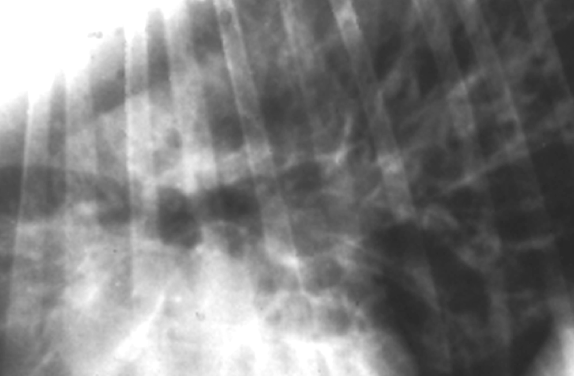

Q

Bronchial